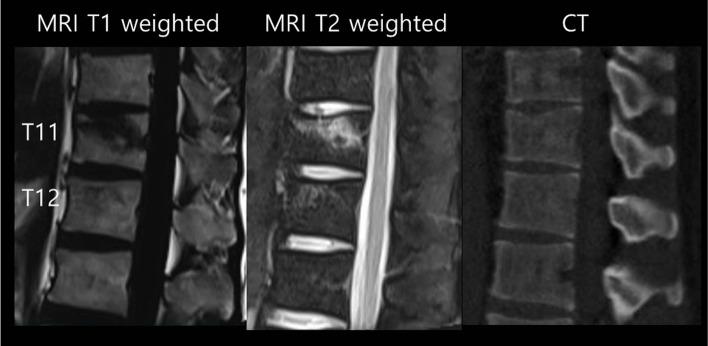

The VBB was defined on MRI as band-like or diffuse zones of high signal intensity on T2-weighted sequences without fracture of the cortex based on CT. The study population with traumatic VBB associated with non-osteoporotic spinal fracture was composed of 15 females and 21 males. The minimal follow-up period was 6 months. The ratio of anterior to posterior heights of the VBB, the ratio of anterior heights of the VBB to the average of those of cranial and caudal adjacent vertebral bodies, the anterior wedge angle of the VBB, and the focal angle around the VBB were compared between the initial and final visits. We evaluated the age of the patients, the C2 plumb line distance, the regional location of VBB, the etiology of VBB, and the treatment methods of the fractures as possible risk factors influencing the progression.

根据 CT,MRI 上的 VBB 定义为 T2 加权序列上的高信号强度带或弥漫带,无皮质骨折。创伤性 VBB 与非骨质疏松性脊柱骨折相关的研究人群包括 15 名女性和 21 名男性。最小随访时间为 6 个月。VBB 的前后高度比、VBB 的前后高度比与颅侧和尾侧相邻椎体平均高度的比值、VBB 的前楔形角和 VBB 周围的焦点角度在初始和最终访问时进行比较。我们评估了患者年龄、C2 铅垂线距离、VBB 的区域位置、VBB 的病因以及骨折的治疗方法作为可能影响进展的危险因素。